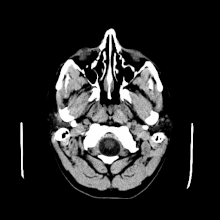

Los quistes coloides pueden diagnosticarse según los síntomas que presenten. Es necesario llevar a cabo análisis adicionales. Los síntomas pueden ser similares a los de otras enfermedades. Para confirmar el diagnóstico, a menudo se utilizan imágenes por resonancia magnética (IRM) o tomografías computarizadas (TC).[5]